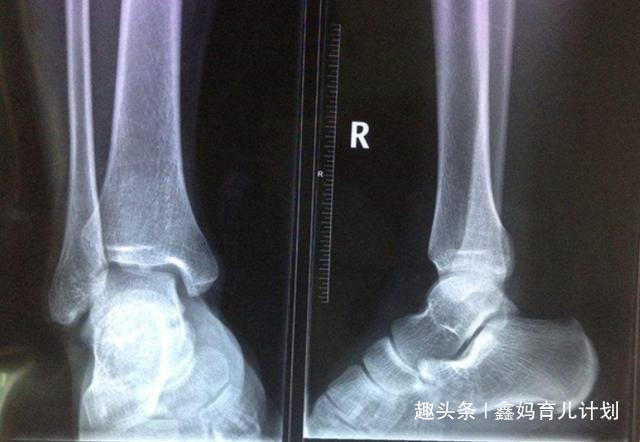

吴女士很不理解,明明女儿吃饭是很正常的,补钙也补了,为什么就是长不高呢?后来去医院做了一个检查之后才发现这竟然是骨骼疑似闭合,这真是给了吴女士一个晴天霹雳。不过好在孩子的骨骼还没有完全闭合,如果抓住机会的话还能够长一长个子。吴女士倒吸了一口凉气,看来想要给孩子长个儿得抓紧了。虽然说骨线闭合是一个比较严重的问题,但是孩子一旦出现这种情况的话,在这之前肯定是有一些信号的。当孩子身上有这3个信号的时候一定不要放弃,把握机会的话个子还是有可能窜一窜。